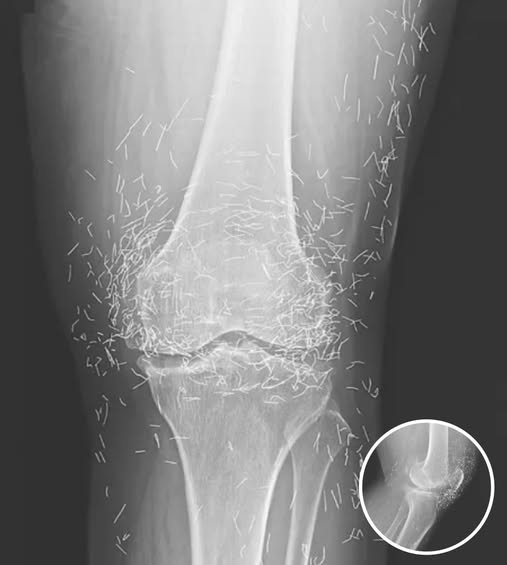

Doctors Stunned After Looking At This X-Ray Of Woman Suffering Joint Pain

A 65-year-old woman in South Korea experienced a shocking medical discovery when doctors found hundreds of tiny gold needles embedded in her knee tissue during a routine X-ray. She had been suffering from chronic osteoarthritis, a condition that causes joint pain, stiffness, and inflammation due to cartilage breakdown.

In this case, the needles were intentionally left in her body as part of a long-term treatment strategy. Some practitioners believe that leaving gold needles or threads in place can provide ongoing stimulation to the affected area. However, medical professionals warn that this approach carries significant risks.

Dr. Ali Guermazi, a radiology expert from Boston University not involved in the case, explained that the human body can react negatively to foreign objects. Inflammatory responses, tissue damage, and infections are potential complications. Additionally, the embedded needles can interfere with medical imaging, making diagnosis more difficult.

One of the most serious risks comes with MRI scans. The powerful magnetic forces used in MRIs can cause metal objects to move within the body, possibly leading to punctured blood vessels or other life-threatening injuries. This makes metal implants a critical concern for patients who may need future imaging.